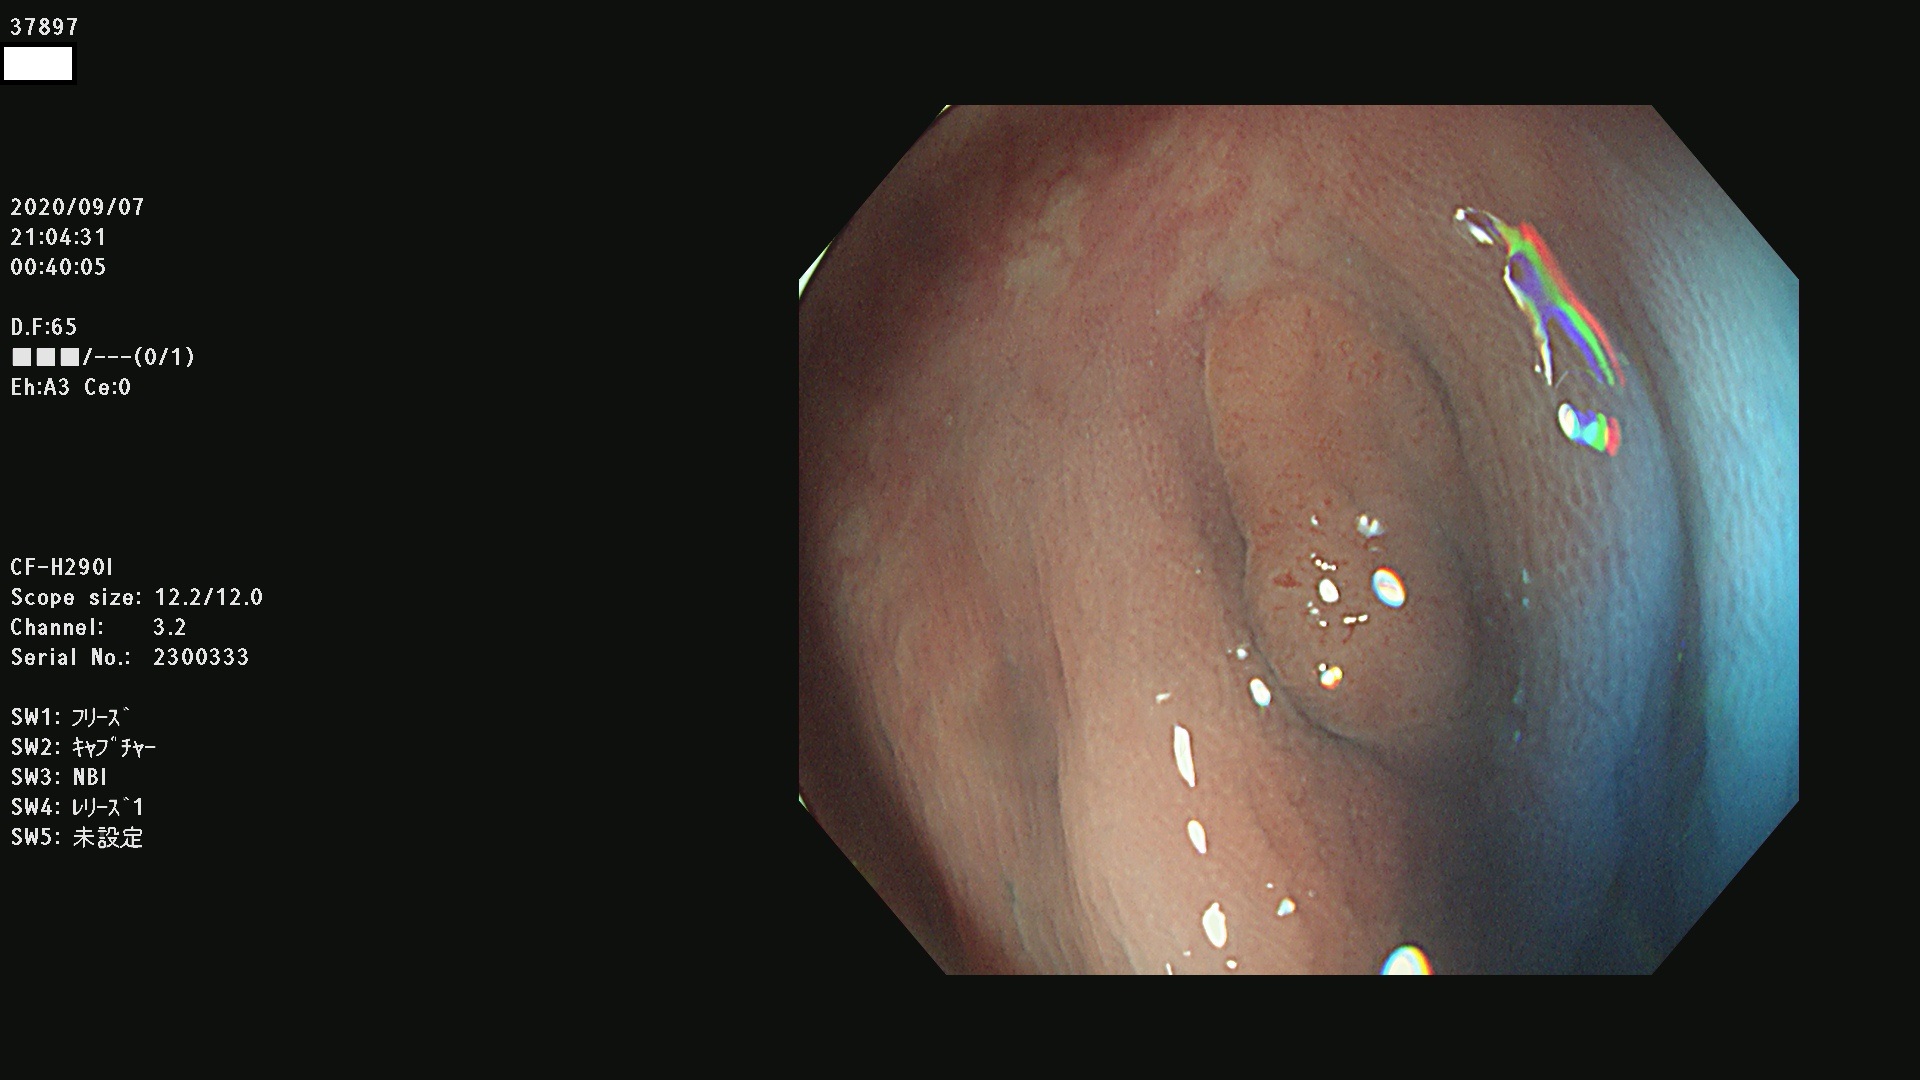

腺腫発見率 75 % (カルテ番号 37800〜37899の100名の方の検査結果で集計)大腸癌検診最新情報

以下のカルテ番号の方に腺腫(Adenoma,Group3〜5)が見つかりました(集計法)

37800(SSAPのみ) 37801 37802 37803 37804 37805 37806 37807 37808 37809(SSAPのみ) 37810 37811 37812 37813 37814 37815 37817 37818 37819 37820 37821 37822 37824 37825 37826 37827 37828 37829 37832 37833 37836 37837(SSAPのみ) 37839 37840 37842 37844 37845(SSAPのみ) 37847 37849 37850 37851 37852 37853(SSAPのみ) 37855 37856 37857 37860 37861 37862 37863 37864 37867 37868 37871 37874 37876 37877 37879 37880 37881 37882 37883 37886 37887 37888 37889 37890 37891 37892 37893 37894 37896 37897 37898 37899

発見困難で危険性の高い平坦型病変(上記100名より抽出) ![]()